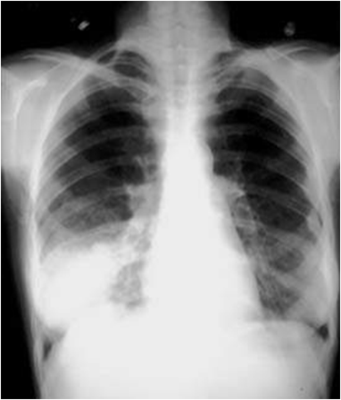

Paciente 68 años, Femenino, sin antecedentes mórbido. Consulta por cuadro de 4 días de evolución caracterizado por tos con expectoración mucopurulenta, disnea progresiva, dolor pleurítico en hemitórax derecho y sensación febril no objetivada. Al examen se evidencia matidez de región afectada, con murmullo pulmonar muy disminuido, sin otros ruidos agregados. Se toma la radiografía adjunta. ¿Qué diagnóstico propondría con estos antecedentes?

Answer

• Derrame Pleural Derecho

• Atelectasia de Lóbulo inferior derecho

• Neumonía base derecha

• Absceso pulmonar derecho